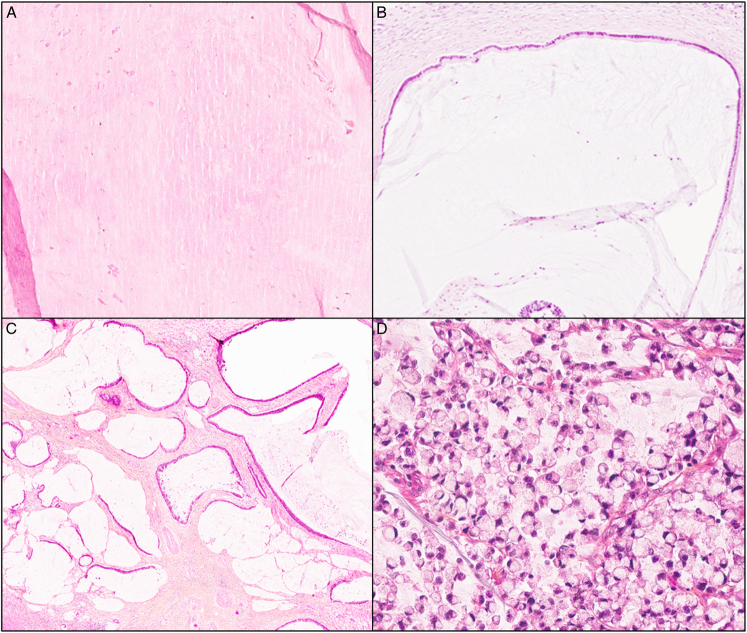

Abstract Image